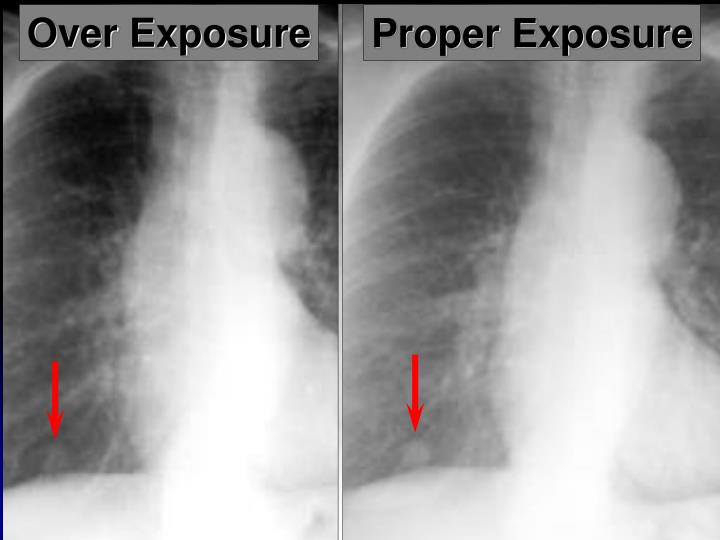

337.4 PA chest xray overexposure Emergency Medicine Clinical Ap Chest X Ray Exposure Erect pa projections are considered the ‘gold. The ap oblique view specifically focuses on the axillary ribs. The rib series is often considered to be an unnecessary, unjustified projection in many radiology. The abcde approach can be used. The left hemidiaphragm should be visible to the spine, and the vertebrae should be visible behind the heart. This literature review was. Ap Chest X Ray Exposure.